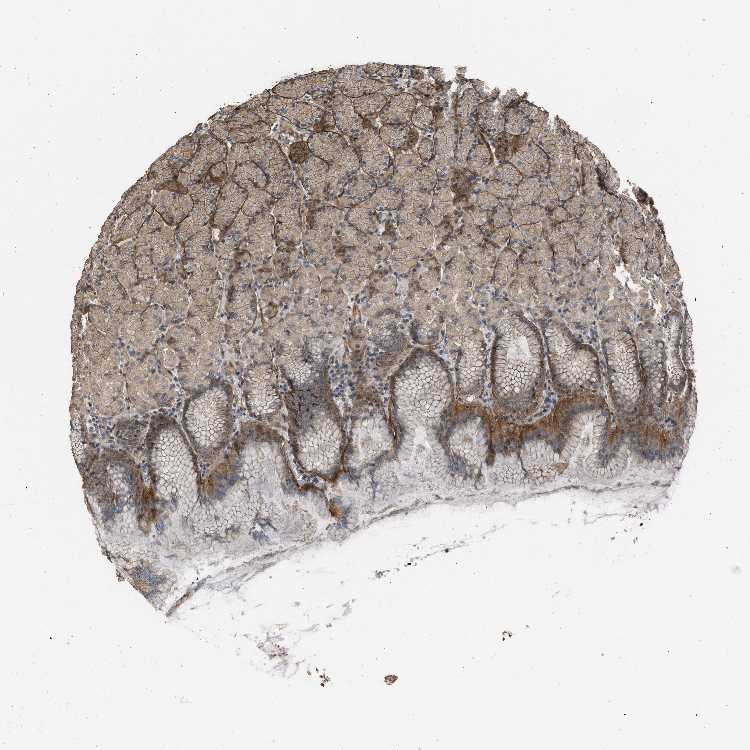

STOMACH 1 - Antibody stainingi

Antibody staining in the annotated cell types in the current human tissue is reported as not detected, low, medium, or high, based on conventional immunohistochemistry profiling in selected tissues. This score is based on the combination of the staining intensity and fraction of stained cells.

Each image is clickable and will lead to virtual microscopy that enables deeper exploration of all samples and also displays staining intensity scores, fraction scores and subcellular localization as well as patient and tissue information for each sample.

Antibody HPA018894Antibody CAB016348

Glandular cells MediumHigh